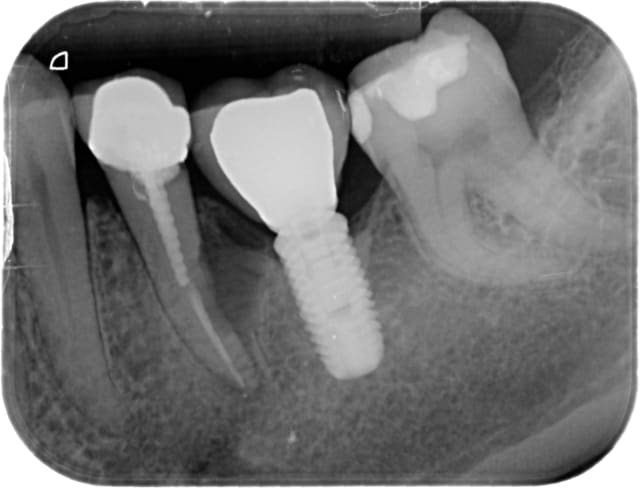

Patient, 20 ans, choc multiples sur les centrales étant gamin. Pano pour les 8.

Lésion sur 21, en bouche, légère dyschromie, test froid négatif, pas de douleur, retro, tu m'étonnes ... ! Les autres répondent correctement.

Concrètement, comment obturer convenablement ça ?

Bouchon de MTA : entre la galère pour appliquer ça correctement à l'apex et sans dépasser dans tous les sens, bof, de plus j'imagine que c'est utopique de vouloir obtenir ne serait-ce qu'un début de fermeture apicale.

Cônes de gutta moulés avec moultes Rx..., pourquoi pas, déjà fait, mais l'étanchéité ne semblerait pas optimale, ajouté au fait que le peu de ciment risque de fuser également.